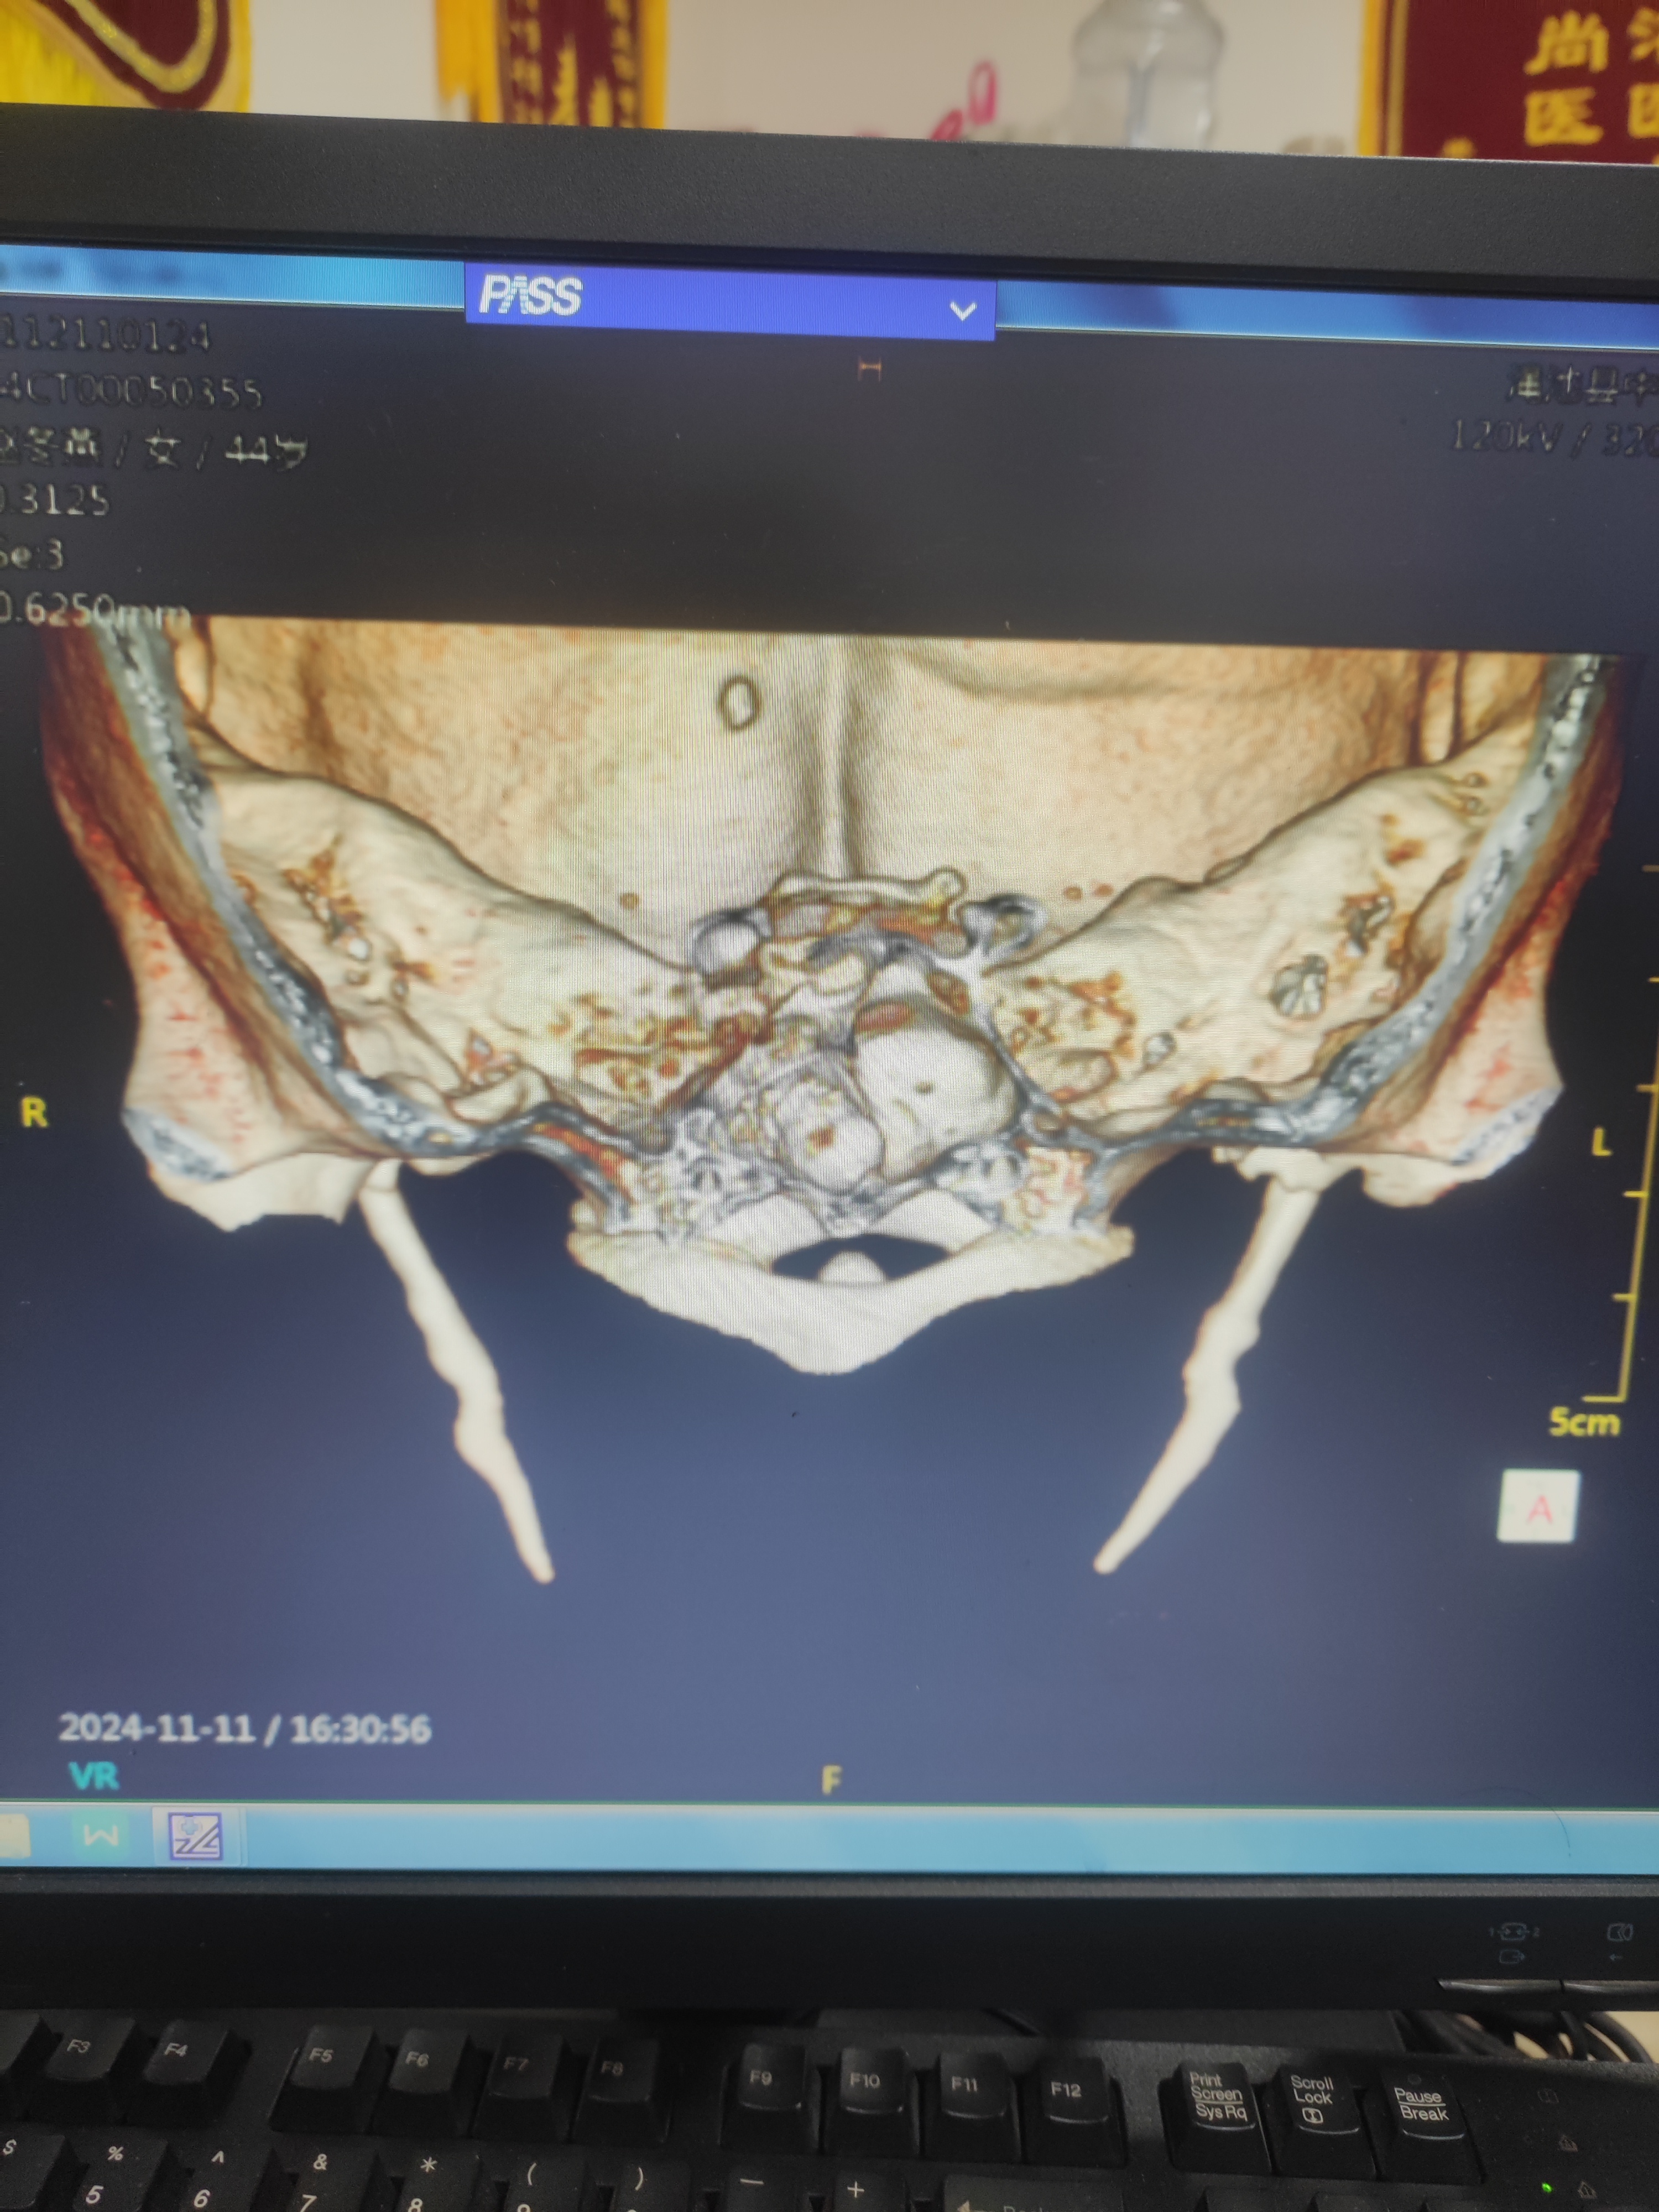

2024年11月11日,我院耳鼻咽喉科門診二室接診一位50歲的女士,訴咽部不適3年,扭脖子時有異物感,像針扎一樣,左右兩側(cè)均有疼痛感,患者用手順著頸部向下擼擼,再慢慢活動頸部,疼痛感會消失。平時服用咽炎類藥物效果不佳。張書梅副主任醫(yī)師詳細詢問病史及行相關(guān)的咽喉檢查后排除慢性咽喉炎,考慮一個引起該癥狀的疾病——“莖突過長綜合征”,建議病人行莖突三維檢查。結(jié)果顯示:右側(cè)莖突5cm;左側(cè)莖突4.6cm;提示莖突過長。(正常莖突在2.5cm左右)。通過檢查后,患者的病癥得到明確的診斷,解決了病人長期困擾的“咽炎”問題。從而明確了治療方案。什么是莖突過長綜合征呢?莖突是位于頸動脈后外側(cè)的細長骨,通過肌腱、肌肉與咽部相連。莖突綜合征病因較多,導(dǎo)致患者成長過程中莖突過長(超過30毫米認為異常),或者傾斜角度過大,進而造成一系列癥狀:如:咽喉部疼痛、咽部有異物感、耳朵疼痛等感覺,這種感覺多存在患者咽部的一側(cè),有時會壓迫頸動脈,引起同側(cè)的頭頸部疼痛,有咳嗽、失眠等癥狀產(chǎn)生,嚴重時會引起大腦缺血。如果有慢性咽炎的患者,經(jīng)長期治療效果不佳者,可到耳鼻咽喉科行全面檢查,以明確診斷及治療。以免耽誤病情。